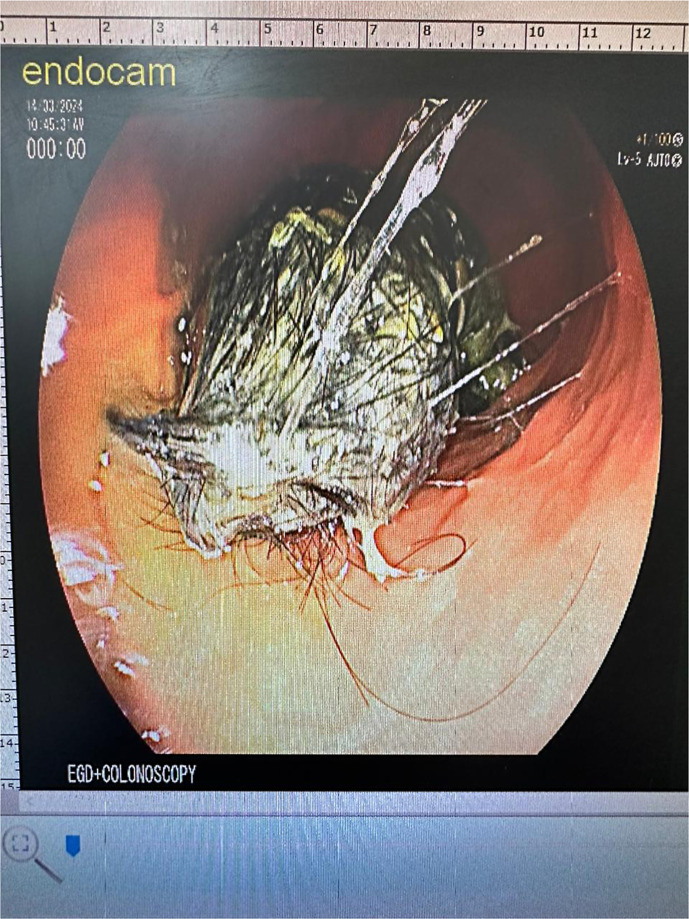

Case presentation: A 7-year-old girl presented with abdominal pain for 6 months associated with occasional vomiting and diarrhea. Family history was positive for ulcerative colitis. Physical examination was unremarkable including normal growth. Diagnostic workup revealed elevated fecal calprotectin at 433.9 mg/kg. Upper and lower endoscopies were performed. A trichobezoar with Rapunzel syndrome was incidentally found in the stomach extending into the duodenum without frank obstruction. Histology showed reactive gastropathy in a few areas of mechanical rubbing by hair strands; otherwise, it was completely unremarkable in both upper and lower GI biopsies. Endoscopic retrieval of piecemeal hair locks was done. Surgical removal was subsequently done due to the generous size of the mass.